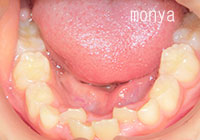

デコボコの歯並びの原因の多くは歯が生える場所が足りないことです。つまり、アゴの成長不足によるものがほとんどです。

歯並び